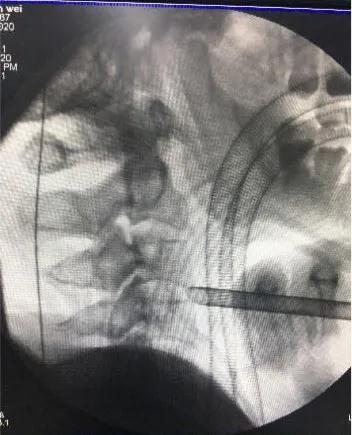

颈前路术术中套管定位